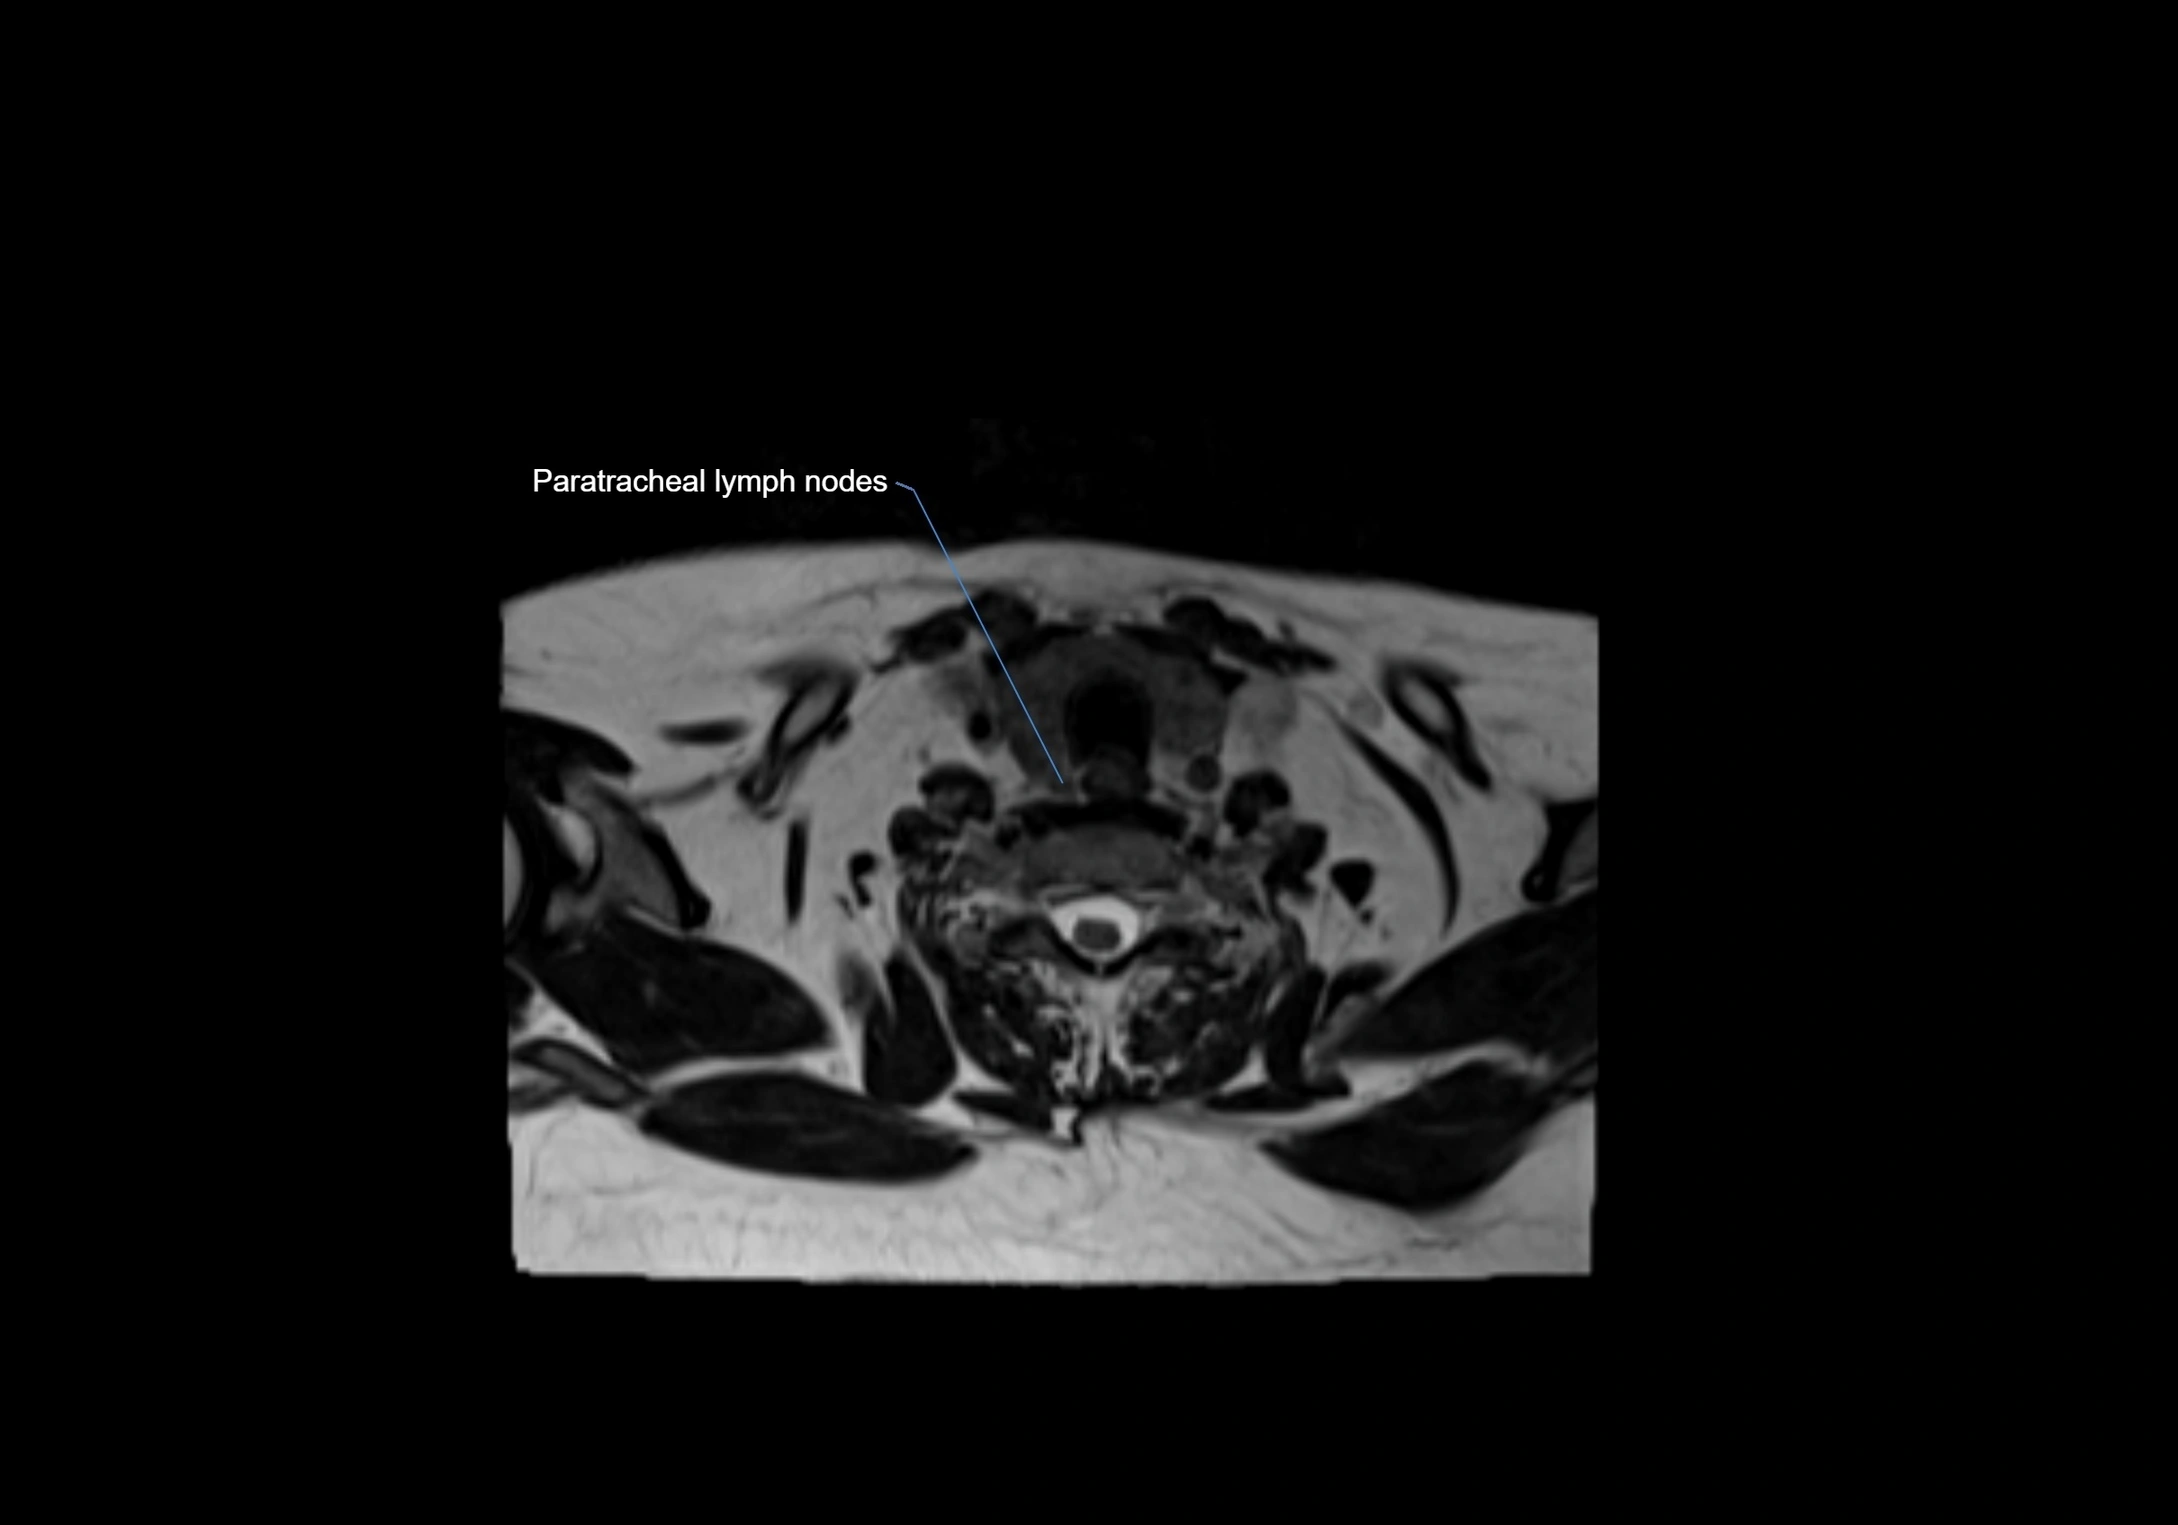

MRI Appearance

T1-weighted images:

• Normal accessory nodes appear as small, oval hypointense to intermediate signal structures within subcutaneous fat

• Surrounded by hyperintense fat, enhancing contrast for visualization

• Pathological nodes may appear enlarged or rounded, sometimes with cortical thickening

T2-weighted images:

• Nodes show intermediate signal, with surrounding fat bright

• Useful for detecting edema, inflammation, or infiltration

• Fatty hilum may appear slightly hyperintense relative to cortex